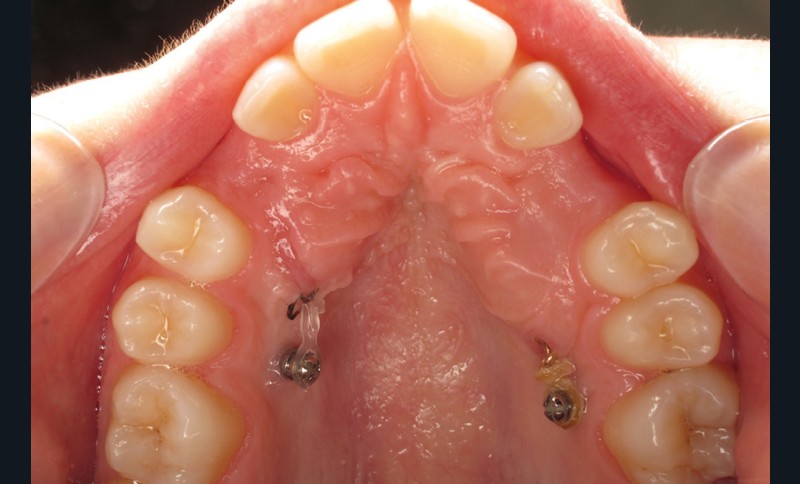

Le Dr Christophe Dunglas développera ensuite l’intérêt du cone beam lors de la mise en place des canines incluses difficiles. En effet, la préparation d’ancrages adéquats et de gestes chirurgicaux a minima préviendra l’apparition de résorptions radiculaires et de lésions parodontales.

À côté de la coopération moindre qu’ils exigent, les ancrages squelettiques présentent également l’avantage de répondre à des indications très variées : correction des sourires gingivaux (Dr Skander Ellouze, fig. 3a-c), distalisation ou mésialisation molaire, supports pour les masques faciaux, mini transpalatin sur vis après expansion, ressorts de rétraction pour mettre en place les canines incluses sans léser les racines des dents adjacentes [3] (Dr Stéphane Renger, fig. 4) ou appareils d’expansion maxillaire (Dr Hans Winsauer, Dr Guido Sampersmans, fig. 5a-c)…